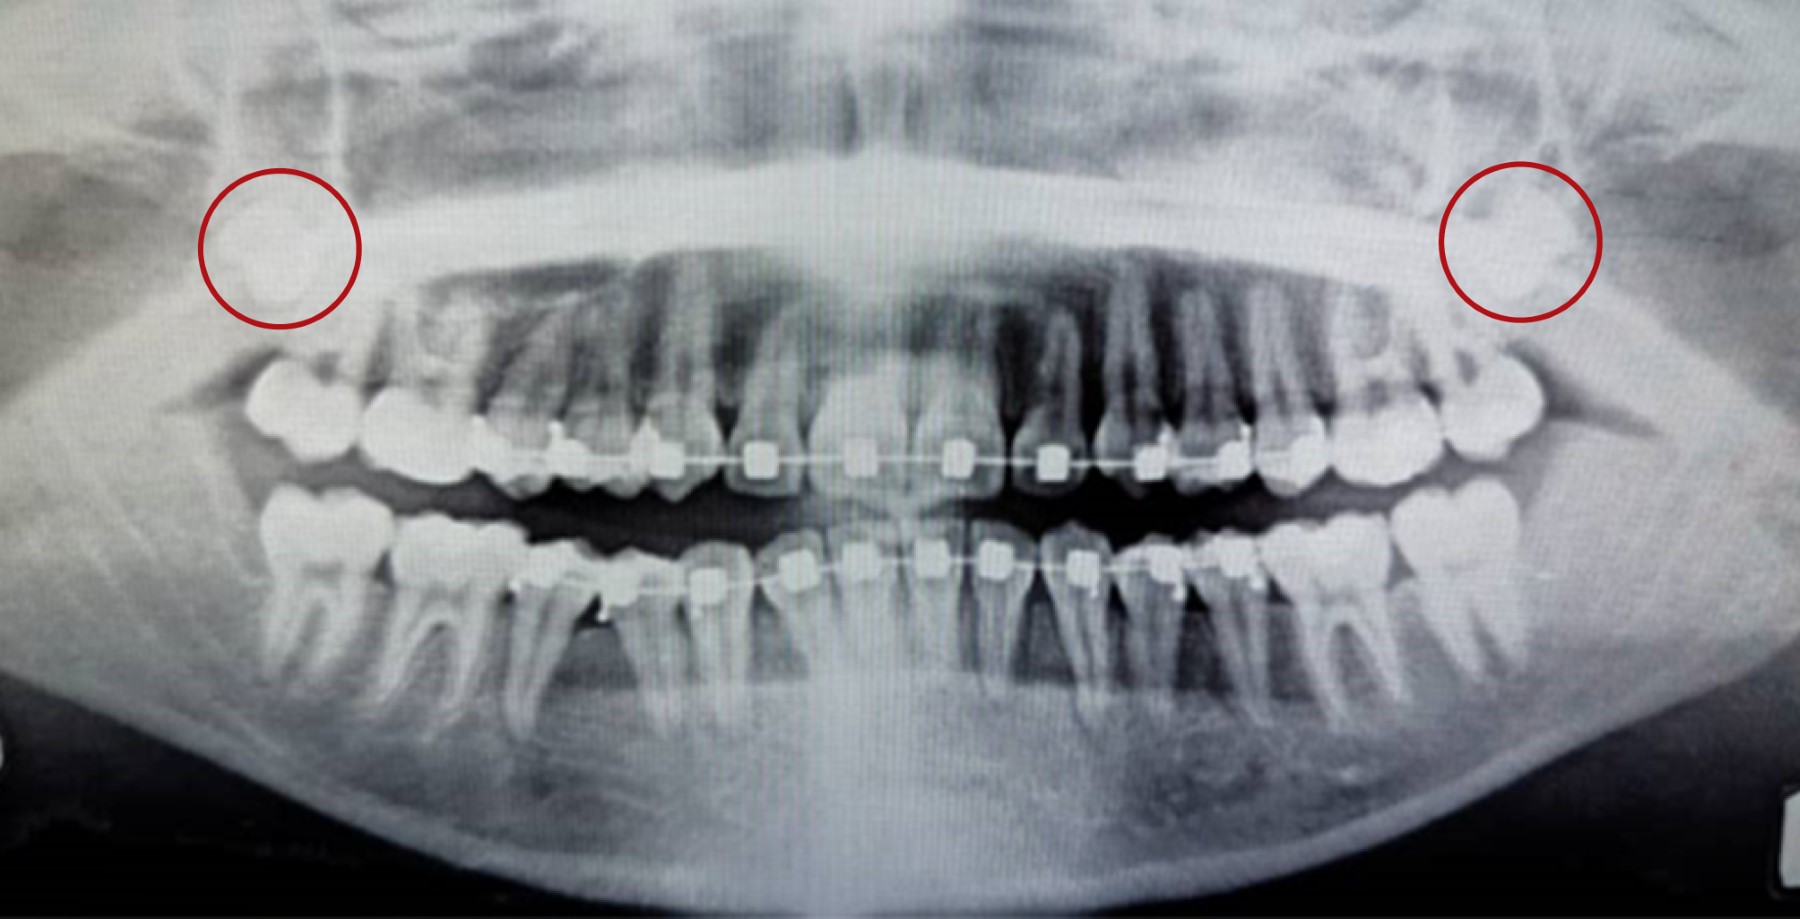

Se trata de un paciente femenino de 16 años de edad, natural y procedente de Caracas, Venezuela, sin antecedentes médicos conocidos, quien acude al Servicio de Cirugía Oral del Hospital Ortopédico Infantil para la valoración y extracción de terceros molares, los cuales clínicamente no se encontraban presentes en boca. Al examen radiográfico se observaron las unidades dentarias (UD) 18 y 28 retenidas en posición vertical según Winter a la altura de la porción apical de la raíz de la UD 17 y 27, respectivamente (Figura 1). Durante la extracción de la UD 28, dicha unidad es perdida de vista por parte del operador, por lo que solicita radiografía panorámica para su ubicación (Figura 2). Se indica antibiótico, analgésico y antiinflamatorio, así como medidas antiedema. Posteriormente, se solicita tomografía de haz helicoidal para su planificación quirúrgica.

Figura 1

Figura 2